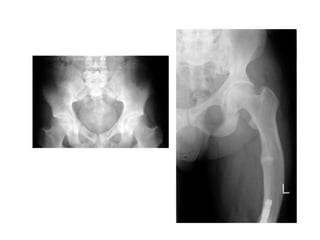

Clinical Features

• In infants, clinical features of hypocalcaemia include

– seizures, apnea, and tetany.

• In children, clinical features of rickets include

– delayed motor milestones

– Hypotonia

– enlargement of wrists

– progressive bowing of long bones, rachitic rosary, Harrison

sulcus, late closure of anterior fontanel, parietal and frontal

bossing, craniotabes

– delay in teeth eruption, enamel hypoplasia, decreased

bone mineral density, myopathy with normal deep tendon

reflexes,

– propensity for infections (as a consequence of impaired

phagocytosis and neutrophil motility).